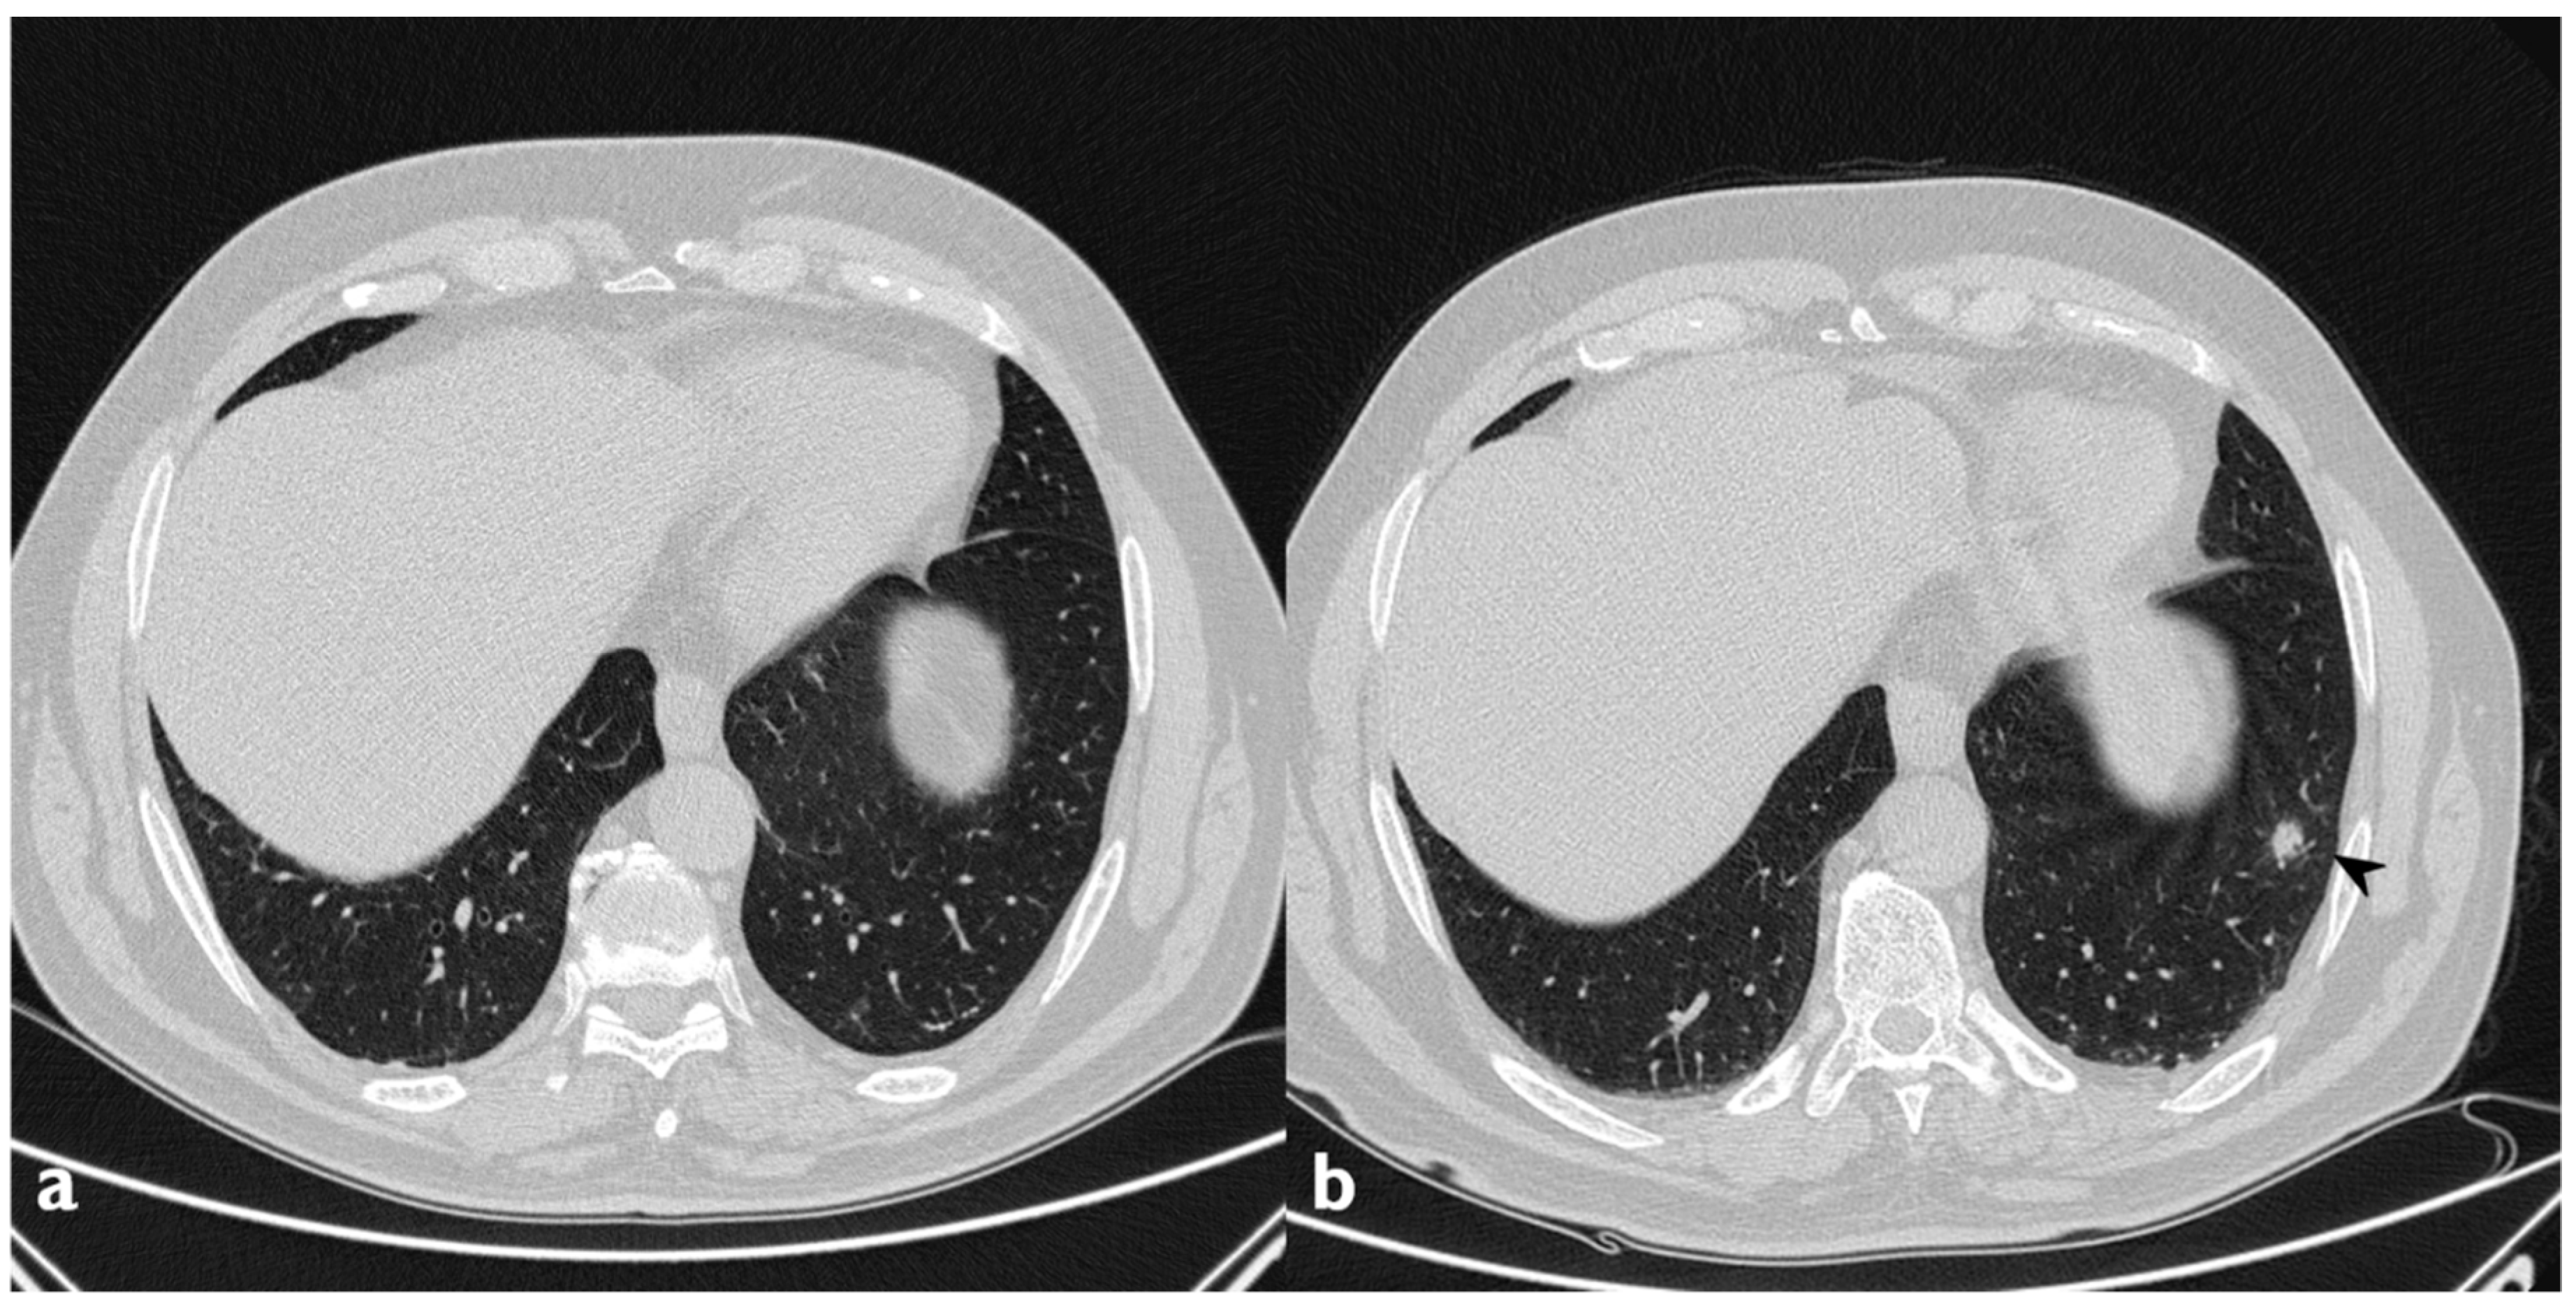

The classical form of COP is characterized by multifocal parenchymal consolidations, often bilateral and asymmetrical. These findings are usually described as patchy or with peripherical or peribronchial predominance in lower lobes. They tend to migrate, disappearing spontaneously and appearing in different sites (Figure 2) [22,26]. Consolidations may be associated with GGOs; usually, these lesions may reproduce an air bronchogram sign in the context [22]. At the moment of the onset, this typical pattern has been encountered in about 75% of patients [22,24,25,26].

Figure 2. Typical pattern: multifocal and asymmetrical parenchymal consolidations (arrowheads), with peripheral distribution. These lesions may reproduce an air bronchogram sign in the context.